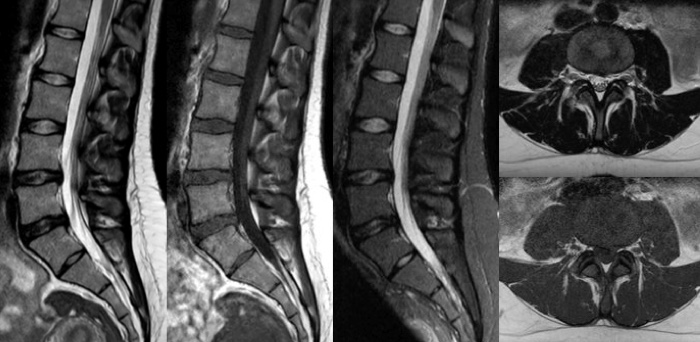

時間を味方につける - Compressed SENSEを使用すると、実質的に同等の画質を保ちつつ、撮像時間を最大50%²短縮できます。空間分解能が60%向上した高品質のMR画像を得ることで確実な診断が可能になります。

Conventional

Compressed SENSE